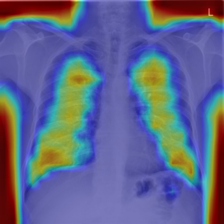

4.7.2 Activation Response Maps

As shown in Fig. 9, given the text lungs, we can find that the activation maps can accurately highlight the target regions. Therefore, we can achieve a higher performance on the downstream tasks. However, the activation maps are imperfect, as the background regions are also highlighted.